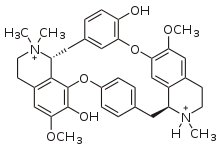

Dimer alkaloids

In addition to the described above monomeric alkaloids, there are also dimeric, and even trimeric and tetrameric alkaloids formed upon condensation of two, three, and four monomeric alkaloids. Dimeric alkaloids are usually formed from monomers of the same type through the following mechanisms:[193]

- Oxidative addition of phenols (dauricine, tubocurarine)